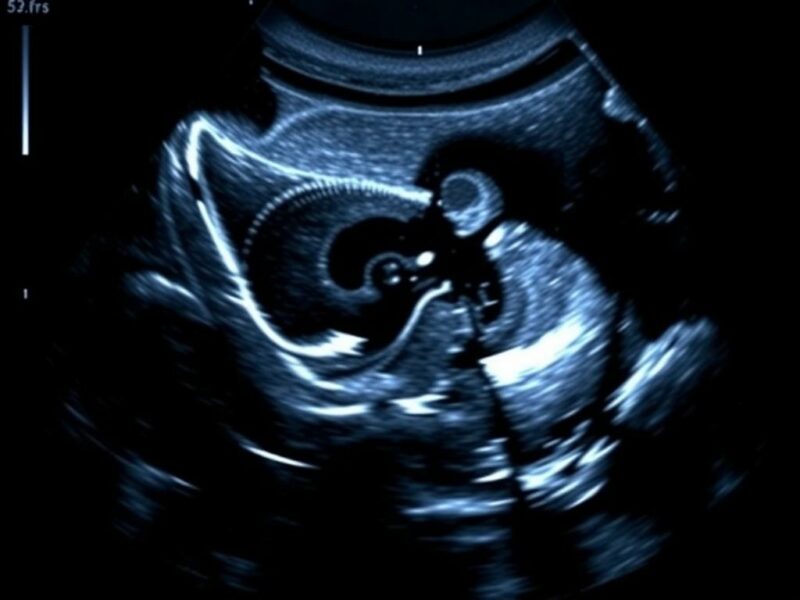

La ecografía, o ultrasonido, usa ondas sonoras de alta frecuencia para formar imágenes de tejidos blandos. Un transductor envía ondas que rebotan en las estructuras internas y regresan, siendo procesadas en tiempo real. Su magia está en la inmediatez: el operador puede mover el transductor, pedir al paciente que cambie de posición, y observar la dinámica de órganos y fluidos en segundos. Es una técnica no invasiva, portátil y, crucialmente, libre de radiación ionizante.

La principal ventaja de la ecografía es su disponibilidad y bajo coste relativo. En muchos consultorios, incluso en urgencias, hay un equipo portátil que permite una evaluación rápida. Además, es especialmente valiosa en manos de un operador experimentado para guiar procedimientos como aspiraciones, biopsias o drenajes, reduciendo complicaciones y evitando radiación adicional que a veces generaría una TC guiada. Otro beneficio es su seguridad en embarazadas y en niños, poblaciones en las que minimizar la radiación es una prioridad.

Por último, la ecografía proporciona información funcional: puede mostrar flujo sanguíneo con Doppler, movilidad de estructuras y cambios inmediatos al aplicar compresión o maniobras dinámicas. Esta capacidad para observar la fisiología en vivo la hace insustituible en muchos escenarios clínicos, desde evaluar la perfusión de un órgano hasta detectar colecciones líquidas o guiar tratamientos mínimamente invasivos. Su relación coste-beneficio y su perfil de seguridad la convierten en la primera línea en numerosos problemas clínicos.

– Embarazo y dolor abdominal: la ecografía es la primera elección para evaluar placenta, líquido libre, embarazo ectópico y apendicitis en manos expertas. Si la ecografía es inconclusa y la sospecha clínica persiste, la RM es una excelente alternativa sin radiación para aclarar dudas.